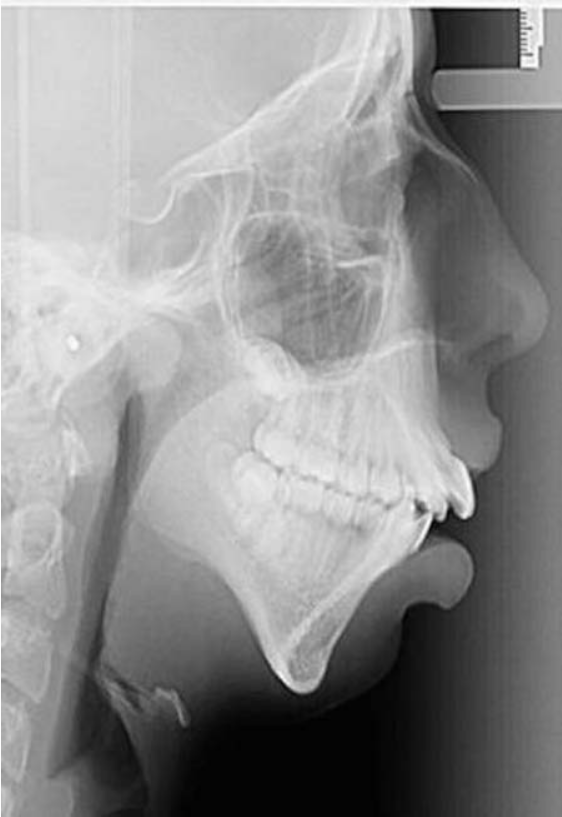

Στο χειρουργείο, που ακολούθησε, το οποίο ήταν δεύτερο κατά σειρά μπόρεσε να διορθώσει το πηγούνι της. Έτσι, μπόρεσε να μεταμορφωθεί και να φτιάξει παράλληλα και την ψυχολογία της.

«Η χειρουργική επέμβαση δεν έχει αλλάξει μόνο τον τρόπο που κοιτάζουν την Ellie, αλλά και τον τρόπο που η ίδια βλέπει τον εαυτό της. Η αυτοπεποίθηση της έχει αυξηθεί και η ίδια έχει εξελιχθεί σε μια όμορφη νεαρή κοπέλα».